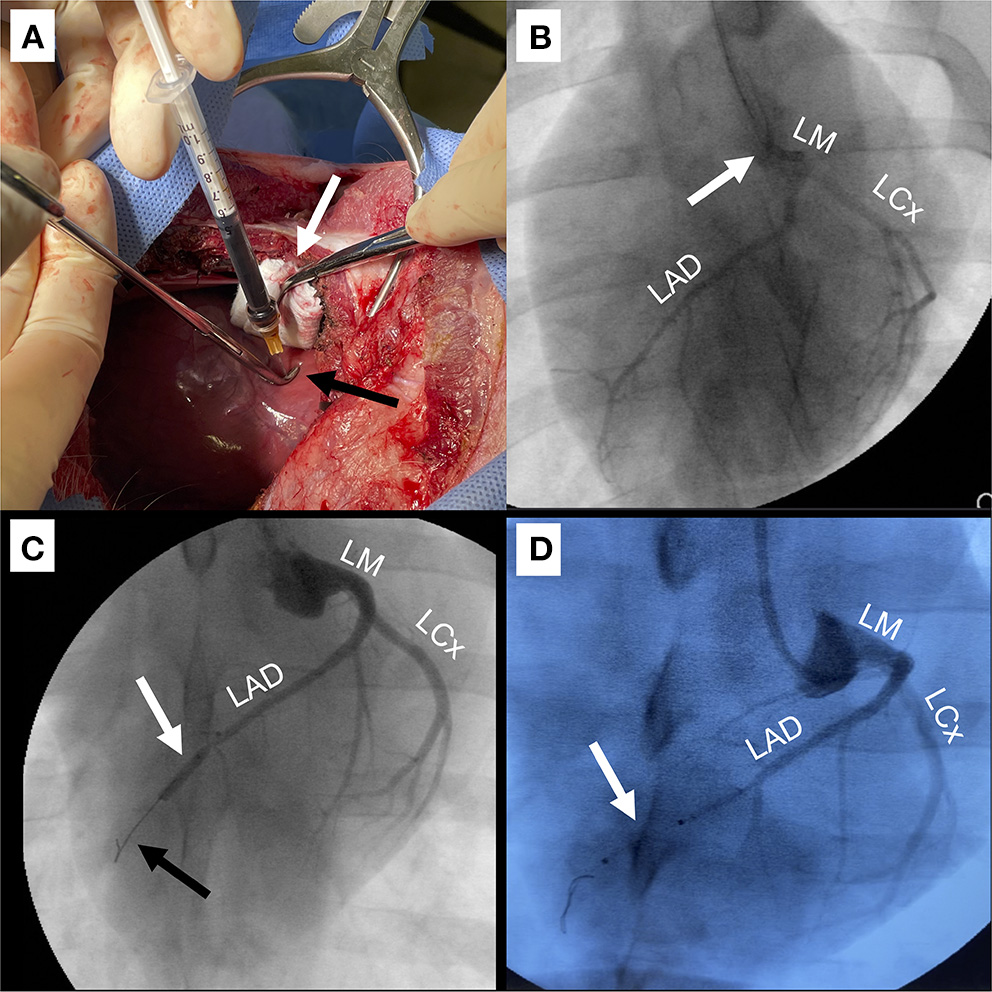

Figure 2

Techniques for delivery of IO/AAV. (A) Intramyocardial injection (IM) through anterior right thoracotomy. The apex was retracted to the right to expose the anterior and apical regions (white arrow) and a 25-gauge 5/8″ needle in a right-angled clamp (black arrow) was used to mediate depth of injection. (B) Direct left main coronary artery infusion (LM). Coronary angiographic catheter (white arrow) was positioned in the LM. Infused radiographic contrast marks targeted coronary arteries including the left circumflex (LCx) and left anterior descending (LAD). (C) Balloon occlusion with distal infusion (BO). Angioplasty balloon was positioned in the mid-LAD (white arrow) and inflated for 60–90 s to occlude distal flow (black arrow), during which IO/AAV was infused through the distal tip of the balloon catheter. (D) Perforated sidewall balloon infusion (SW). IO/AAV was infused through the sidewall of a non-occlusive perforated balloon (white arrow) positioned to extend from the mid- to distal-LAD.